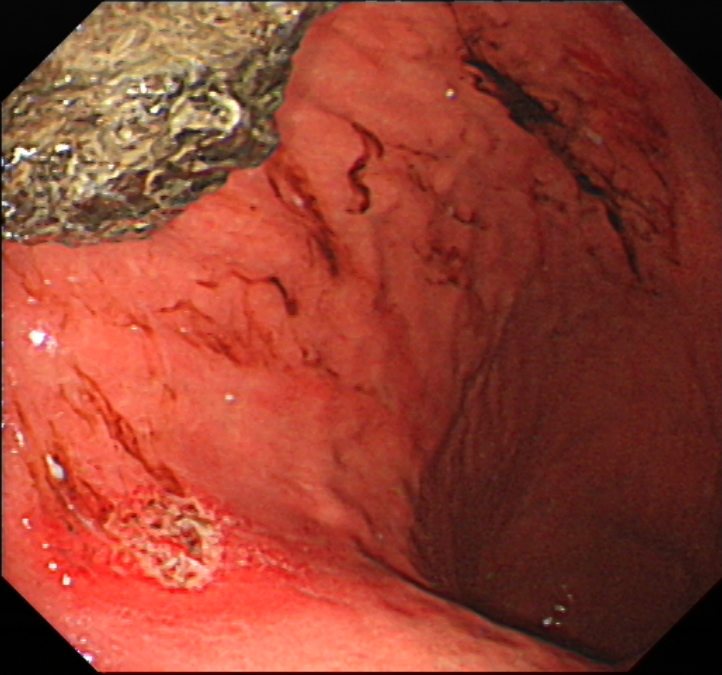

-胃石症合并溃疡-

部分病人可因胃石引起机械性摩擦、压迫损伤,从而导致胃粘膜糜烂、溃疡、出血,或也可能排入肠道导致肠梗阻。

-内镜下治疗-